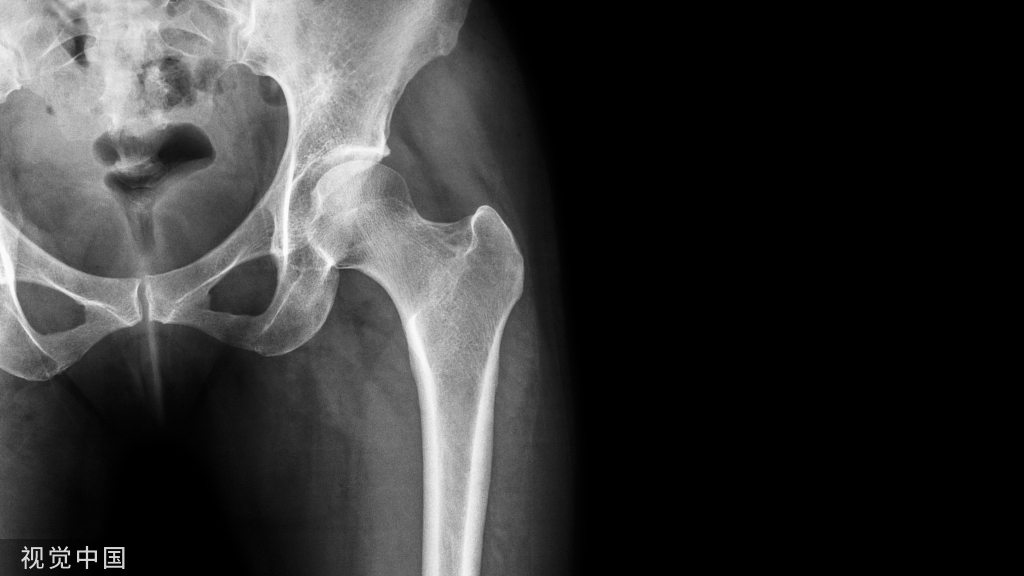

01、“手动版”复位需依靠人力和经验

不同于普通的股骨、胫骨等直线型骨骼,骨盆结构特殊,顾名思义,骨盆呈环状,像一个盆一样,一旦骨折,其修复难度可想而知。传统的骨盆修复往往依靠外科手术,要求医生切开骨折部位,在布满血管神经的骨盆部位显露出骨折位置,并通过徒手操作复位骨折,最后使用钢板固定。这种方式创伤大,需要麻醉、输血,且恢复时间长。随着医学的进步,如今的骨科手术追求的是微创,损伤小、恢复快。

在智能化骨折复位机器人发明以前,“手动版”的骨盆微创复位手术方式需要多人配合,至少得4个大夫,因为骨盆修复要把骨折线对上,这就需要一定的张力,得有一人负责牵拉上肢,一个人负责牵拉下肢,通过拉伸产生的张力,让骨盆周围的软组织、韧带、肌肉的约束力使骨折自动回位,同时术者还要在X线透视下反复调整骨折位置,一旦判断复位满意,则所有人把持住不动,再由一个有经验的医生打临时固定针,将骨盆结构框住。

复位的过程总是让医生累得满头大汗。打好固定针之后,再在放射线的帮助下给破裂的骨缝打上螺钉进行修复固定。手术要做得好,很大程度上得靠主刀医生的经验,整个手术下来,往往需要花费三四个小时,让医生筋疲力尽。